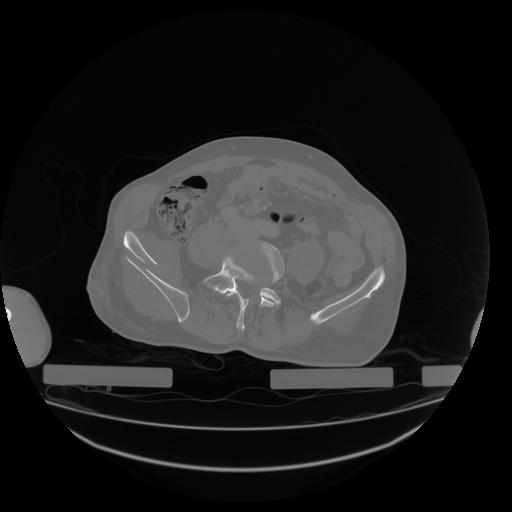

27 CUERPO,CE,Axial,3.0,CUERPO,,